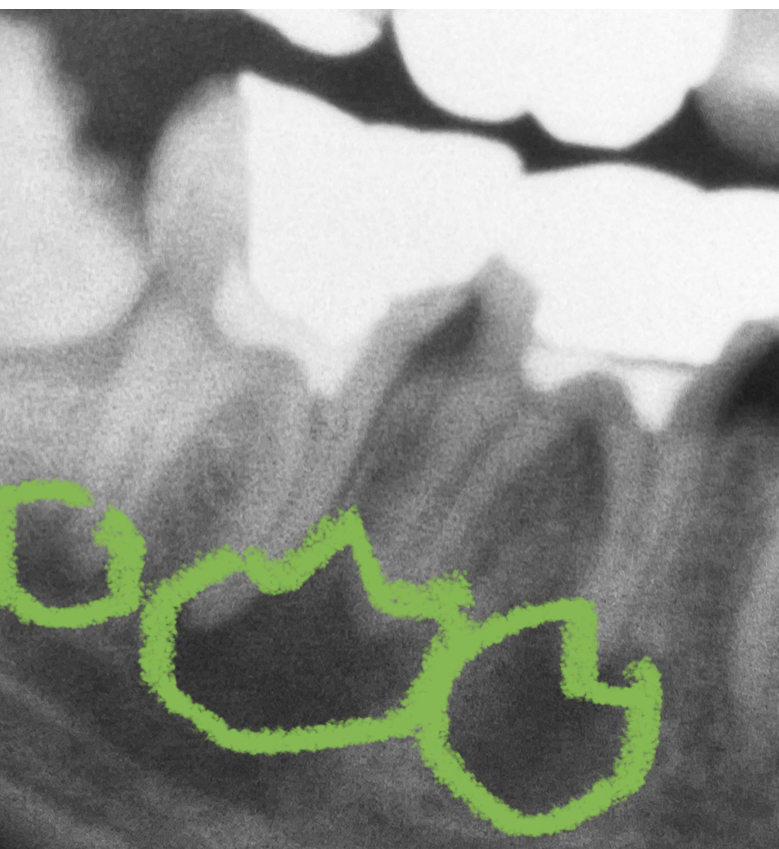

下の図の黄緑色の丸いラインで囲まれた部分に、(右下奥歯の歯根の先端部分の歯槽骨内に)炎症が疑われます。